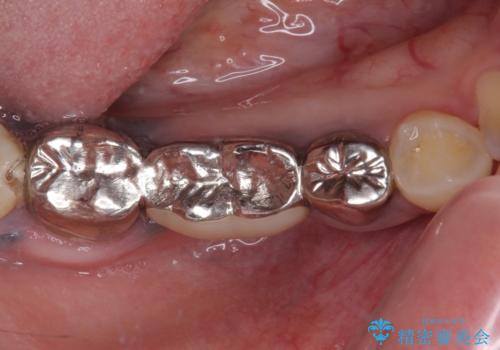

むし歯だらけの奥歯 セラミッククラウンによるむし歯治療

臼歯部メタルフリー再補綴